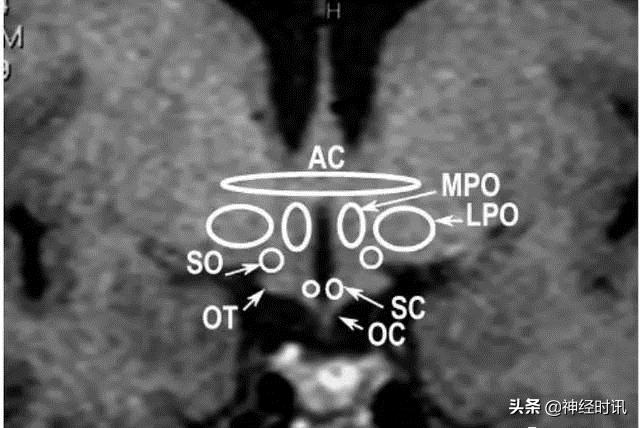

颅脑冠状面MRI表现

A:弓状核;AC:前联合;DM:背内侧核;L:外侧核;LPO:视前外侧核;MB:乳头体;MPO:视前内侧核;P:后核;OT:视束;OC:视交叉;SC:视上核;F:穹窿;PV:室旁核